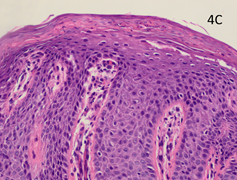

Figure 4A Pre-RT x 100 showing psoriasiform hyperplasia, loss of the granular layer and inflammation.

The pre-RT baseline biopsy was compared with the biopsies taken at eight weeks. The classic histological features of psoriasis are shown in the pre-RT biopsy (Figure 4A-C). There is psoriasiform hyperplasia and inflammation. The epidermis is thickened (a finding known as acanthosis), there is a loss of the normal granular layer, there is a thickened stratum corneum (a finding known as hyperkeratosis), and retention of nuclei in the upper layers and stratum corneum (a finding known as parakeratosis). There is suprapapillary thinning. There are abundant neutrophils in the epidermis and stratum corneum. In the dermis, there are abundant mononuclear cells, predominantly myeloid cells and T cells. There are several dilated dermal blood vessels which give the psoriasis plaques their characteristic erythema.3